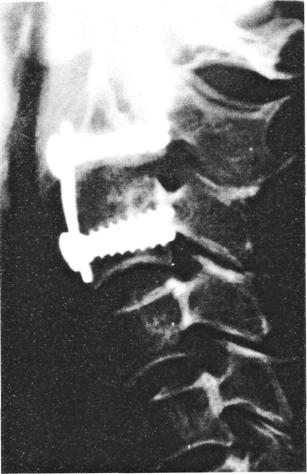

A gerincsérülések konzervatív kezelésének korlátai miatt már a múlt század végén megjelentek a sérült gerincoszlop műtéti úton történő stabilizálására való törekvések. Wilkins, Hadra, Lange, Albee, Hibbs es Ghormley, Mixter, Osgood, Gallie és Cloward munkássága mérföldkő volt a korszerű gerincsebészet kialakulásában. Intenzíven keresték a gerinc stabilizálásához szükséges anyagokat, és így kerültek felismerésre az autolog és homolog csont, a rozsdamentes acél, a vitallium, a titán, a metilmetakrilát. a kerámia és egyéb műanyagok, mint lehetséges belső rögzítő anyagok. A nyaki gerinc betegségek konzervatív és sebészi kezelésében további előrelépést jelentett Nickel és Perry 1959-ben bemutatott hallókészüléke. A scoliosis sebészeteben alkalmazott Harrington, Luque, Jacobs eszközök a traumás gerinckörképek ellátásában csak szükségmegoldásként, erre alkalmasabb eszközök hiányában kerültek alkalmazásra. Roy-Camille transpedunculáris technikája a legkorszerübb stabilizáló eljárások elődjeinek tekinthető. A 70-es évek végetől napjainkig a nyaki és a thoracolumbalis gerinc sérülések ellátásának módszerei és eszközei egyenletes fejlődést mutatnak, amelynek legkiválóbb képviselői: Magerl, Dick, Kluger, Naka-nishi, J. Bonier Caspar, Grob, Jeanneret, Aebi. Stejfee, Cotrel es Dubousset, Edwards, Zielke, Isola a 80-as évek közepétől alkalmazták a legkorszerűbb VSP-lemezes és hosszúrudas rendszereket, amelyek egyben transpedunculáris eszközként is használhatók. Dwyer, Zielke, Dunn, Kaneda, Haas, Yuan a 80-as évek elején fejlesztették ki ventrális stabilizáló eszközrendszereiket. A 90-es évek elejétől ismert a Sqfa-mor-Danek Z-lemez, mint a jelenlegi egyik legkorszerűbb ventrális stabilizáló eszköz.